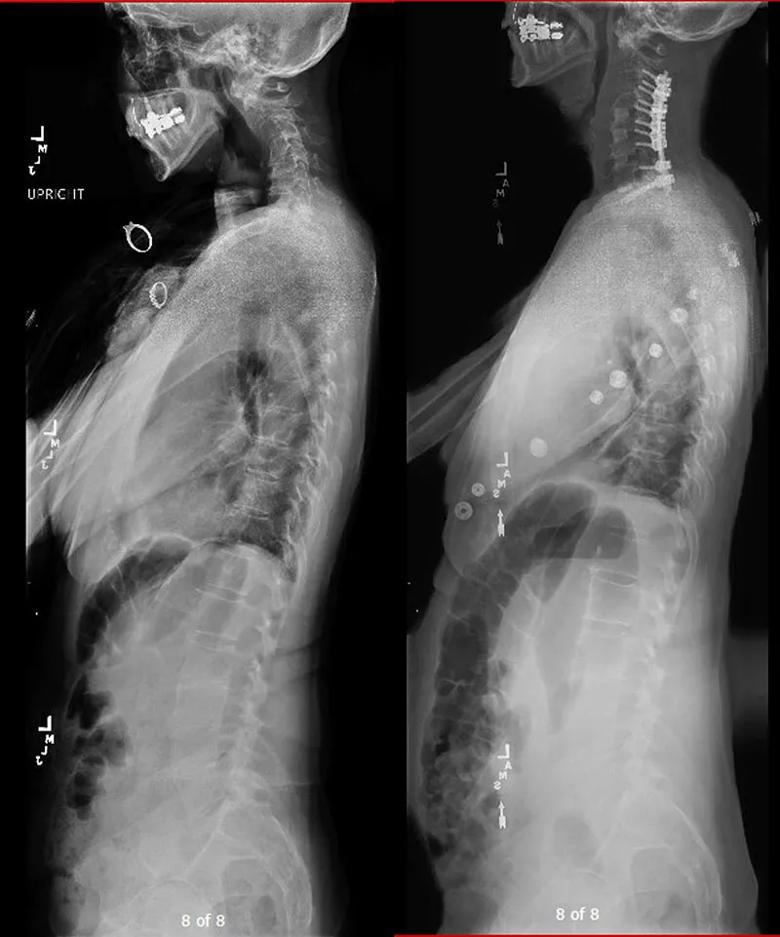

The patient underwent an anterior cervical discectomy fusion from C4 to T1 and posterior column osteotomies and fusion from C3 to T1. Figures 1 and 2 present pairs of preoperative and postoperative imaging studies showing the deformity correction. Dr. Mroz notes that the operation required “nuance to the technique, which enabled correction of the patient’s deformity. Had we not backed up the anterior procedure with additional posterior screws and rods, she may have gone on to develop a nonunion at one of the disk spaces, with loss of the correction.”

Figure 1. Preoperative (left) and postoperative (right) full-length spine X-rays demonstrating correction of cervical kyphosis.